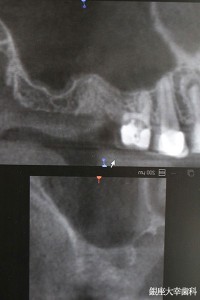

CT撮影とシミュレーションを行います。

シミュレーション通りにオペが出来るようにガイドを作成します。

ガイドを使って正確にインプラントを埋入します。左の図はフラップレス用ガイドです。右はフラップ手術用のガイドです。基本的にはフラップレスの方が負担も少なく良好な経過が得られます。